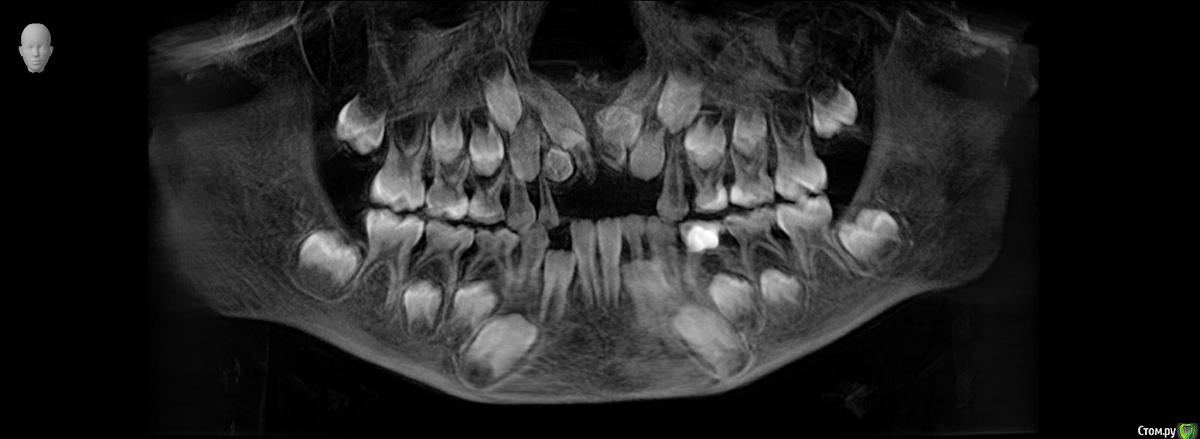

Ребенок 6 лет.

Буду благодарна за Ваше видение картины сверкомплектных и возможные планы варианты лечения.

По теме интересует какие лишние зубы можно дождаться и удалить после прорезывания, какие требуют оперативного вмешательства, какие сроки, тот что на месте 11 не вниз корнем?

Были в 4 клиниках, случай не типичный, варианты лечения разные. От ничего не делать ждать, до резать удалять. Начинали с 2 сверхкомплектов, потом нашли еще два.